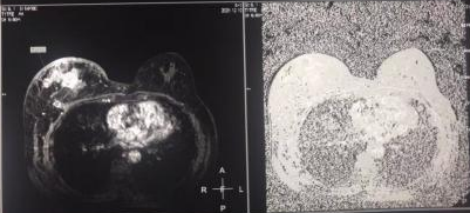

2021年12月10日,乳腺核磁影像表现:左乳明显变形,其内可见多发结节及肿块影,大小不等。最大者约6.3×4.8×5.1cm。形态不规则,信号不均匀,边缘可见分页周围腺体结构紊乱。累计临近皮肤,皮肤明显不规则增厚。

诊断:1、右乳恶性肿瘤(多灶),局部累及皮肤伴右腋下淋巴结转移(BI-RADS:6)。2、左乳腺体增生。3、左腋下多发小淋巴结。

图2.双侧乳腺核磁